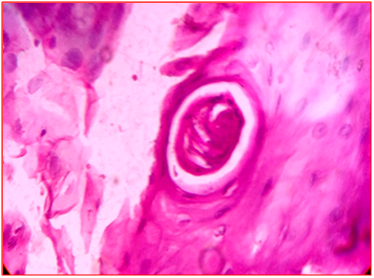

Figure 10 Squamous cell carcinoma H&Eon Fnac, frozen section X10, X10,

Figure 11 Well differentiated squamous cell carcinoma on H&E, x40.